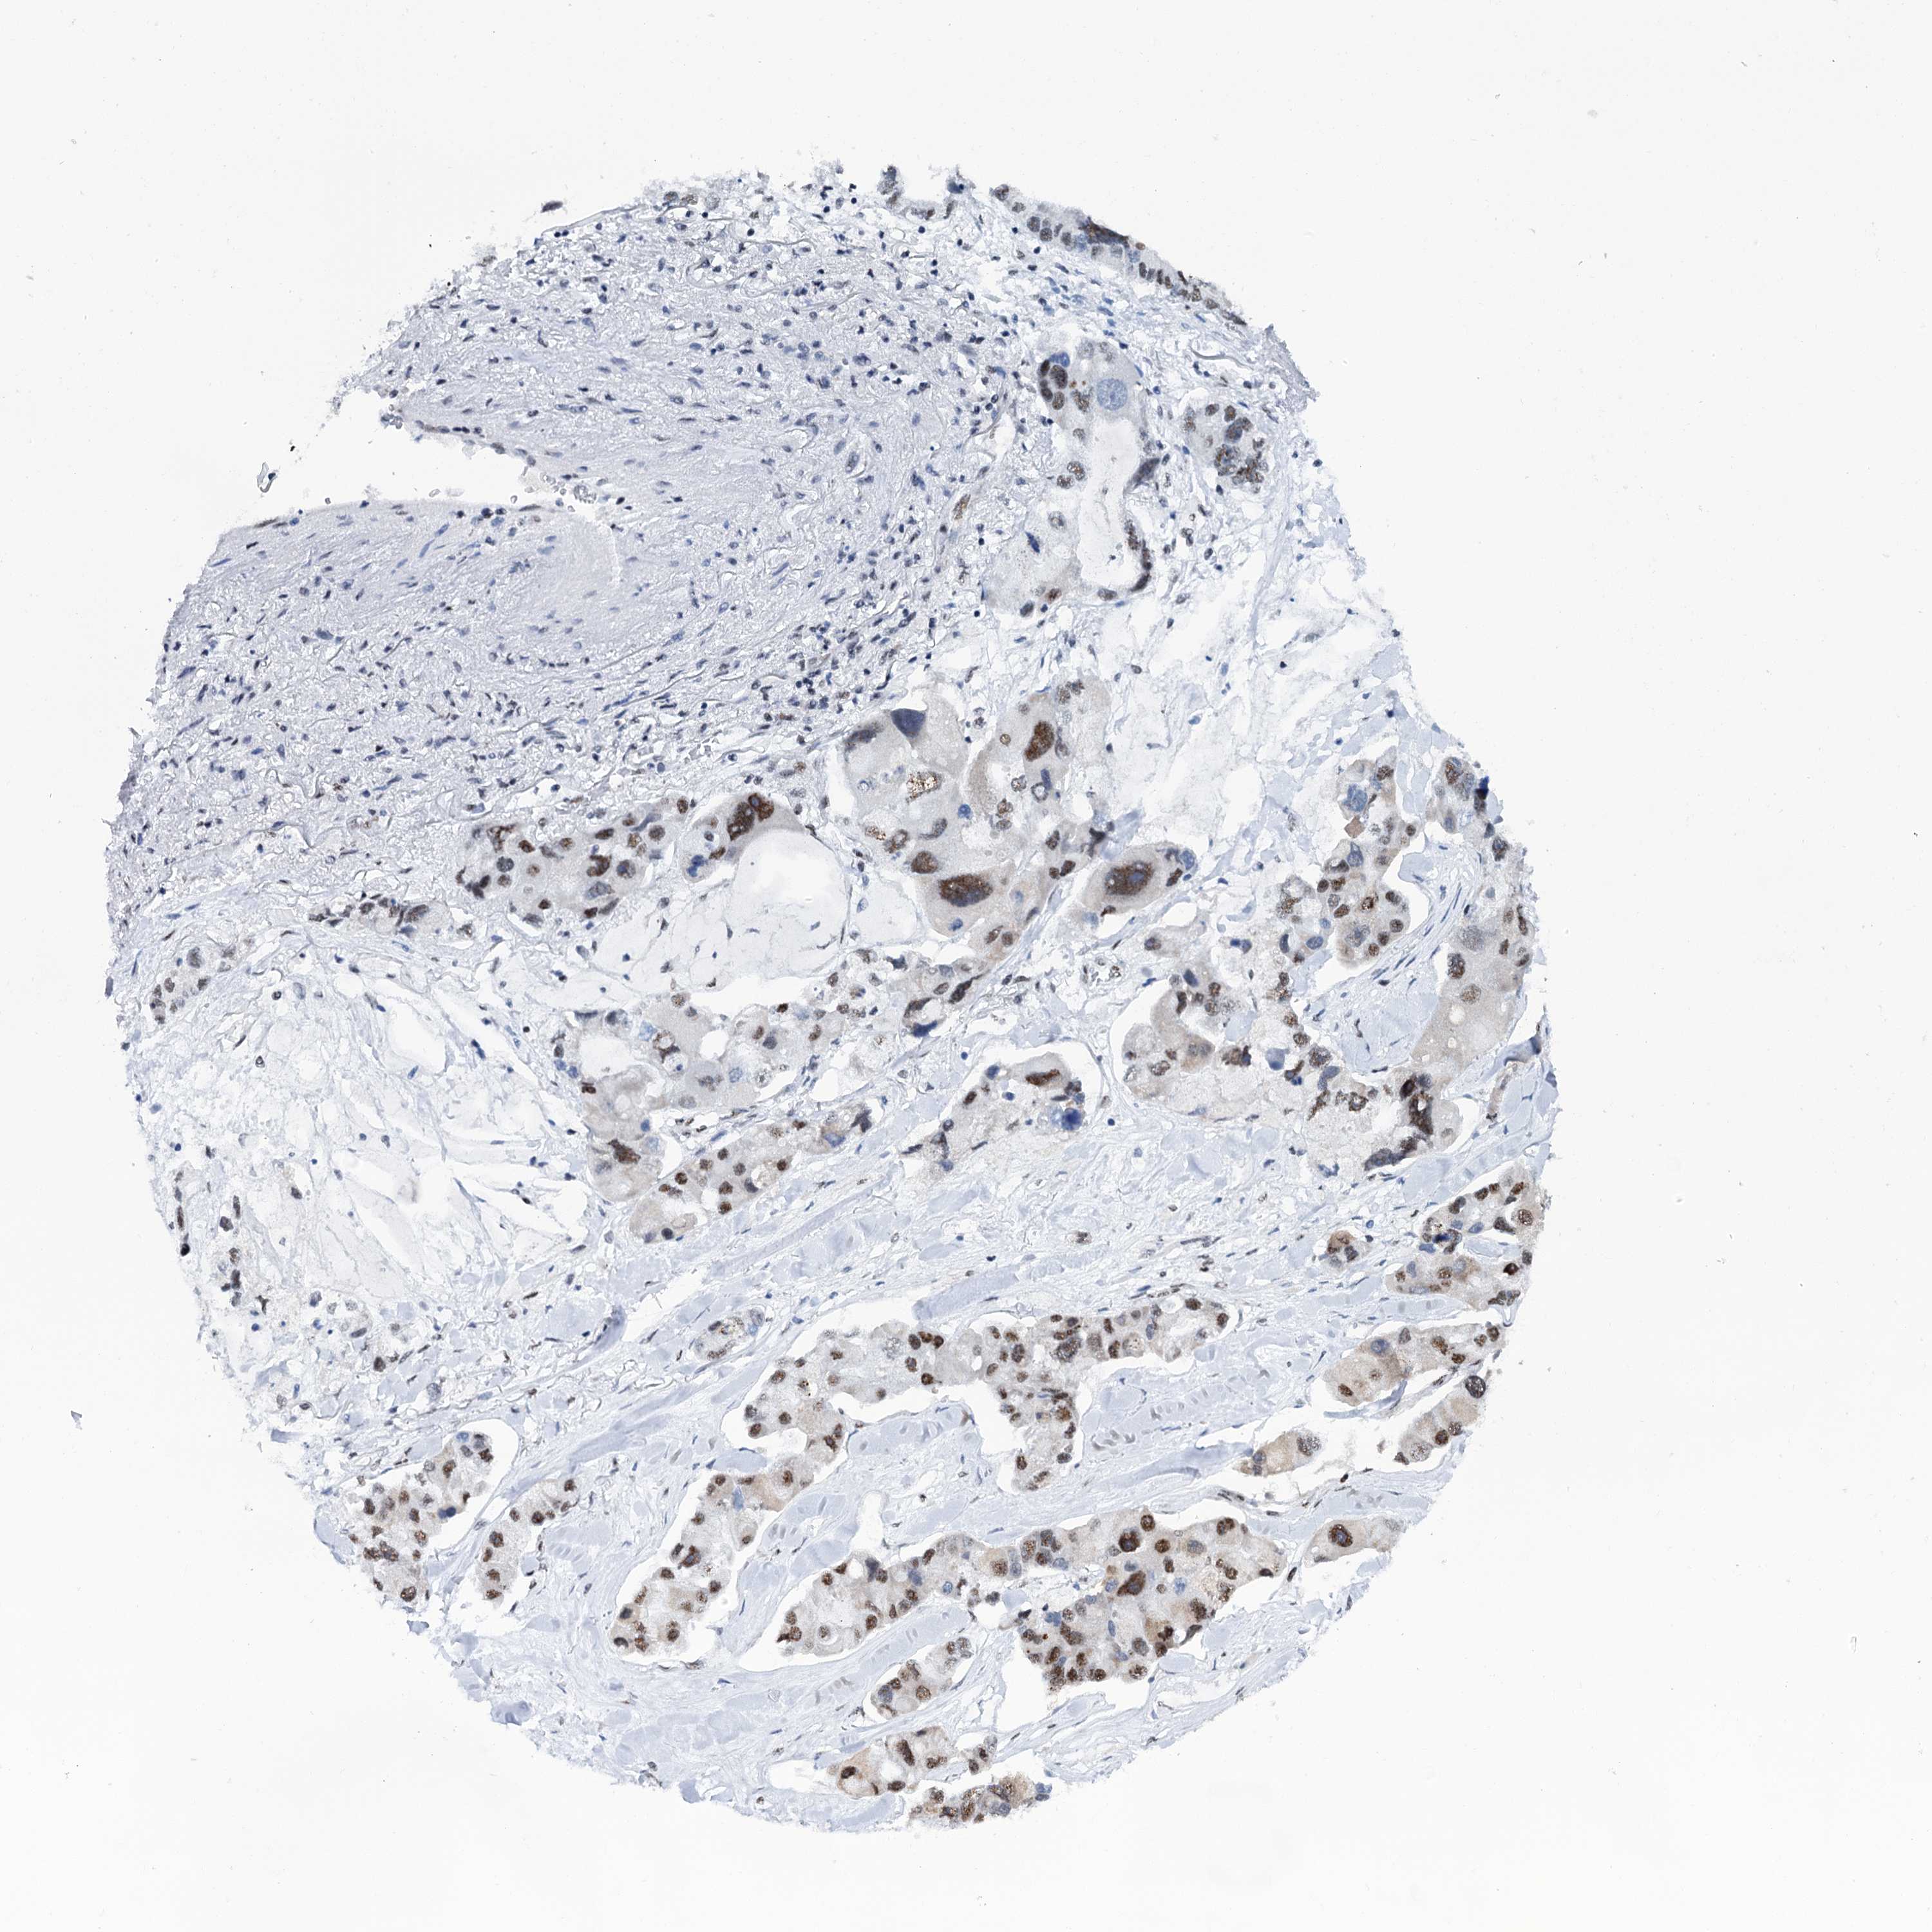

LUNG ADENOCARCINOMA (VALIDATION) - Interactive survival scatter ploti

The Survival Scatter plot shows the clinical status (i.e. dead or alive) for all individuals in the patient cohort, based on the same data that underlies the corresponding Kaplan-Meier plots. Patients that are alive at last time for follow-up are shown in blue and patients who have died during the study are shown in red.

The x-axis shows the expression levels (FPKM) of the investigated gene in the tumor tissue at the time of diagnosis. The y-axis shows the follow-up time after diagnosis (years). Both axes are complimented with kernel density curves demonstrating the data density over the axes. The top density plot shows the expression levels (FPKM) distribution among dead (red) and alive patients (blue). The right density plot shows the data density of the survived years of dead patients with high and low expression levels respectively, stratified using the cutoff indicated by the vertical dashed line through the Survival Scatter plot. This cutoff is automatically defined based on the FPKM cutoff that minimizes the p-score. The cutoff can be changed by dragging the vertical line or by entering a cutoff value in the square labeled "Current cut-off".

Under the Survival Scatter plot the p-score landscape (black curve; left axis) is shown together with dead median separation (red curve; right axis). Dead median separation is the difference in median mRNA expression between patients who have died with high and low expression, respectively. It is calculated as follows: median FPKM expression of dead patients with high expression - median FPKM expression of dead patients with low expression. This is intended to aid the user in visually exploring custom cutoffs and the associated p-scores and dead median separation.

Individual patient data is displayed and can be filtered by clicking on one or more of the category buttons on the top of the page. Categories describing expression level and patient information include: high, low, alive, dead, female, male and tumor stages. The scale of the x-axis can be toggled between linear and log-scale by clicking on the "x log" button. Mouse-over function shows TCGA ID, patient information and mRNA expression (FPKM) for each patient.

& Survival analysisi

Kaplan-Meier plots summarize results from analysis of correlation between mRNA expression level and patient survival. Patients were divided based on level of expression into one of the two groups "low" (under cut off) or "high" (over cut off). X-axis shows time for survival (years) and y-axis shows the probability of survival, where 1.0 corresponds to 100 percent.

SREK1 is not prognostic in Lung Adenocarcinoma (validation)

Best expression cut offi

Based on the FPKM value of each gene, patients were classified into two groups and association between prognosis (survival) and gene expression (FPKM) was examined. The best expression cut-off refers the FPKM value that yields maximal difference with regard to survival between the two groups at the lowest log-rank P-value. Best expression cut-off was selected based on survival analysis .

When clicking on this number, the vertical dashed line indicating cut-off, the interactive survival plot, and the Kaplan-Meier curve will be adjusted to show results based on the best expression cut-off.

: 4.21

Median expressioni

Median expression refers to the median FPKM value calculated based on the gene expression (FPKM) data from all patients in this dataset. When clicking on this number, the vertical dashed line indicating cut-off, the interactive survival plot, and the Kaplan-Meier curve will be adjusted to show results based on the median expression.

: N/A

P scorei

Log-rank P value for Kaplan-Meier plot showing results from analysis of correlation between mRNA expression level and patient survival.

N/A

5-year survival highi

5-year survival for patients with higher expression than the expression cutoff.

For melanoma and glioma, 3-year survival is shown.

5-year survival lowi

5-year survival for patients with lower expression than the expression cutoff.

Average pTPM 6.1

Number of samples 105